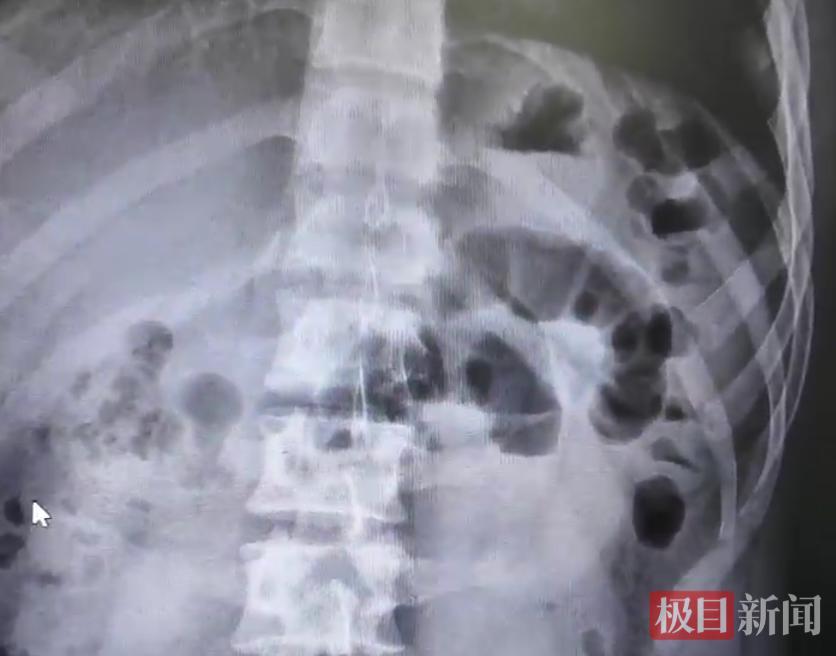

CT检查(受访者供图)

经过腹部CT检查,李阳被确诊为典型小肠梗阻,病因正是短时间内过量进食胡萝卜,肠道堵塞。